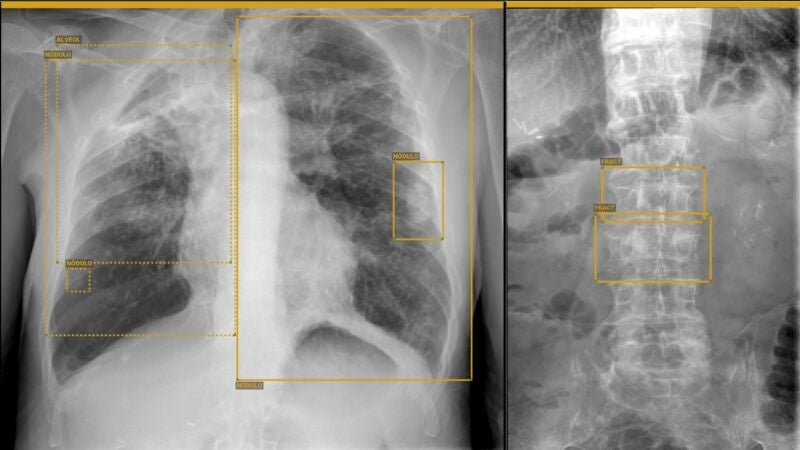

Entre ellas se podrán valorar lesiones óseas traumáticas y tumorales, además de patologías en el entorno de la ortopedia y la rehabilitación (dismetrías o escoliosis…) y la radiología de tórax que se realiza en el ámbito de Urgencias (neumonías, tumores, derrames, etc.).

Con su implantación se consigue que sea la IA la que realice unos cálculos necesarios para conocer los grados de escoliosis o diferencia de altura en la cadera del paciente, entre otros aspectos. Esto lo suele llevar a cabo el rehabilitador, cuyo tiempo puede ahora invertir en una mayor atención en el paciente.

Asimismo, se optimiza el tiempo de respuesta del especialista y aumenta la confianza y la seguridad de la prueba diagnóstica, ya que la IA ayuda al profesional que está realizándola, proporcionando una doble visión de la prueba y localizando con mayor probabilidad una patología, aumentando la calidad diagnóstica del paciente.